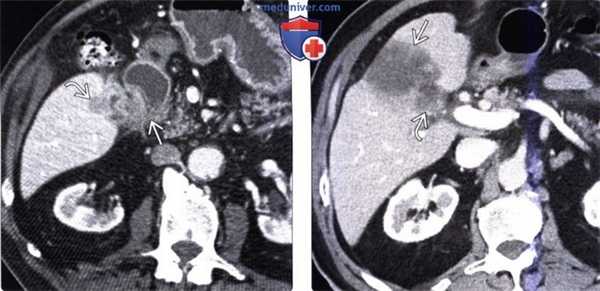

(Слева) На аксиальной КТ с контрастным усилением определяется рак желчного пузыря с инвазией в печень и нисходящую часть двенадцатиперстной кишки. Такие опухоли, если признаются резектабельными, однозначно требуют выполнения расширенной холецистэктомии и радикальной резекции.

(Справа) На аксиальной КТ с контрастным усилением визуализируется объемное образование в ямке желчного пузыря, прорастающее в печень. Во многих случаях, в том числе и в этом, место происхождения опухоли сложно определить.

(Слева) На аксиальной КТ с контрастным усилением определяется выраженное неравномерное утолщение стенки желчного пузыря, непосредственная инвазия печени, а также перипанкреатическая/портокавальная и забрюшинная лимфаденопатия. Увеличение лимфатических узлов этих групп является типичным проявлением рака желчного пузыря.

(Справа) На аксиальной КТ с контрастным усилением визуализируется большое гиподенсное образование в печени. Это образование может быть опухолью печени, однако желчный камень в его центре и невозможность визуализации желчного пузыря позволяют предположить, что образование представляет собой рак желчного пузыря с инвазией печени.